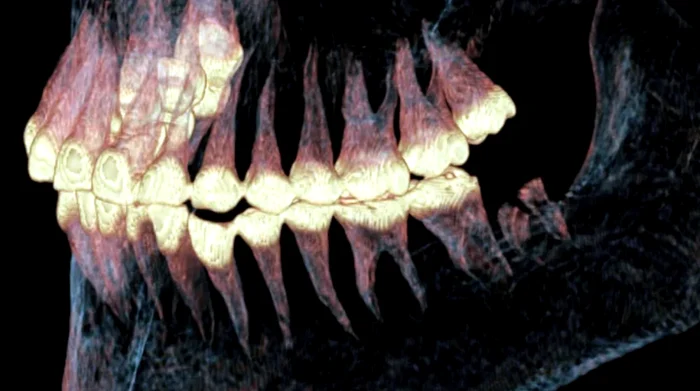

Cercetătorii au folosit scanări CT pentru a privi în interiorul unui craniu parțial mumificat și au descoperit că femeia a supraviețuit acestei intervenții chirurgicale la maxilar realizată acum 2.500 de ani.

Analiza a arătat că vindecătorii antici au perforat canale fine în oasele articulației și au introdus păr de cal sau tendon animal pentru a stabiliza mandibula. Această metodă a funcționat ca o proteză, permițând refacerea parțială a funcției maxilarului.

Cercetătorii au ajuns la aceste concluzii folosind imagistica modernă, care a permis examinarea fără deteriorarea mumiei.

Dovezile biologice arată clar că intervenția a fost un succes. Țesut osos nou s-a format în jurul canalelor perforate, semn al vindecării, iar uzura accentuată a dinților de pe partea stângă indică faptul că femeia a trăit suficient de mult pentru a se adapta noii condiții.